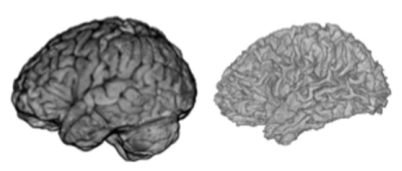

Mindboggle (mindboggle.info) is open-source software for the analysis (feature extraction, labeling, and morphometry) of human brain imaging data. Features include anatomical regions (like gyri and subcortical regions), sulcal folds, and fundus curves. Shape measures include two types of depth, two types of curvature, volume, thickness, Zernike moments, Laplace-Beltrami spectra, etc. The project has been funded by three NIH grants, and is maintained by the Computational Neuroimaging Lab at the Child Mind Institute.

TJ Tustison, PA Cook, A Klein, G Song, SR Das, JT Duda, BM Kandel, N van Strien, JR Stone, JC Gee, BB Avants. Large-scale evaluation of ANTs and FreeSurfer cortical thickness measurements. NeuroImage. 99:166-179 (2014). doi:10.1016/j.neuroimage.2014.05.044